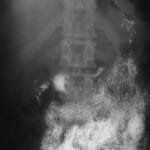

Surgery for small bowel obstruction is a very common emergency operation done in many hospitals. Intestinal obstruction is a blockage of your small intestine or colon that can prevent food and liquid through it. Intestinal obstruction can occur due to a number of conditions, including attachments in the abdominal tissue (adhesions), hernias and tumours or fibrous belts.

Intestinal obstruction may cause unpleasant symptoms, including abdominal pain and swelling, nausea, and vomiting series. If left untreated, it can cause formation of toxins due to stagnant contents. This may result in the death of intestinal tissue, severe infection, shock, and perforation. However, due to institution of timely medical care the obstruction can often be successfully treated.

Signs and symptoms of intestinal obstruction include:

- crampy abdominal pain that comes and goes

- Nausea

- Vomiting

- Diarrhea

- Constipation

- no stool or fart

- abdomen (stomach) swelling